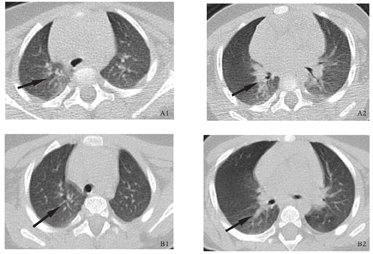

辅助检查:2月5日血常规:白细胞6.2×109/L,中性粒细胞百分比27.7%,淋巴细胞百分比60.1%,中性粒细胞计数1.72×109/L,淋巴细胞计数3.73×109/L,血红蛋白117 g/L,血小板252×109/L;C-反应蛋白7.81 mg/L,降钙素原0.05 μg/L;肝功能、肾功能、血气电解质、心肌酶谱、凝血功能均正常。胸部CT(发病第3天):左肺上叶尖后段、左肺下叶少量斑片状磨玻璃影,考虑感染,病毒性肺炎待排查(图2A1、图2A2)。乙型流感病毒核酸检测阴性,呼吸道合胞病毒、腺病毒、副流感病毒抗原阴性,肺炎支原体抗体IgM阴性。粪常规未见异常。2月10日(发病第8天)胸部CT:左肺上叶尖后段、左肺下叶磨玻璃影,考虑感染,较2月5日略有减少(图2B1、图2B2)。2月12日(发病第10天)血常规:白细胞8.7×109/L,中性粒细胞百分比43.9%,淋巴细胞百分比48.7%,中性粒细胞计数3.82×109/L,淋巴细胞计数4.24×109/L;超敏C-反应蛋白0.32 mg/L,降钙素原0.034 ng/ml;血气电解质、肝肾功能、心肌酶谱、凝血功能正常。

A1、A2:患儿发病第3天,胸部CT提示左肺上叶尖后段、左肺下叶少量斑片状磨玻璃影;B1、B2:患儿发病第8天,胸部CT提示左肺上叶尖后段、左肺下叶磨玻璃影较前减少。